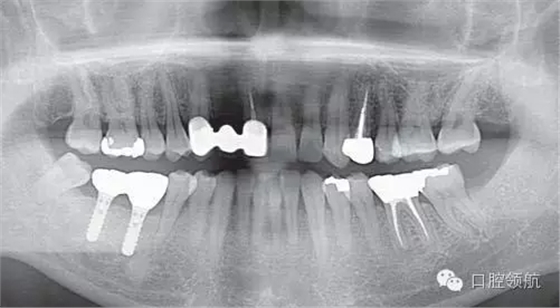

(右下第七、六顆牙)種植體植入術(shù)后(圖1),(右下第七、六顆牙) 拔牙后4個月植入種植體,埋入時,使用動度測量儀測量ISQ值為(左下第六顆牙):70∕70;(左下第七顆牙) :75∕75,顯示了良好的初期穩(wěn)定性,6周后又重新測定了ISQ值為: (左下第六顆牙) :70∕70;(左下第七顆牙):79∕79,遂取印模,制作上部結(jié)構(gòu)(圖2)。因為考慮需要2周的技工制作時間,所以計劃在埋入后2個月安裝最終的上部結(jié)構(gòu)修復(fù)體

圖1 種植體植入后的曲面斷層片。